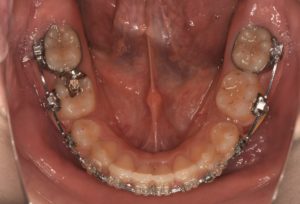

治療から約1年半が経過しました 。

前回の更新でお話したインプラント(アンカースクリュー)を使用して歯の隙間を閉じる工程 、

専門的に言うと space close の治療が重ねられ 、現在の歯並びはこのような状態になりました ↓

こうして見てみると抜歯を行ったところが隙間を閉じていくことによって

うまっていっているのがわかりますね🤔

まだ少し隙間が残っているものの 、抜歯後の状態↓ と比べるとその差がわかりやすいと思います💡